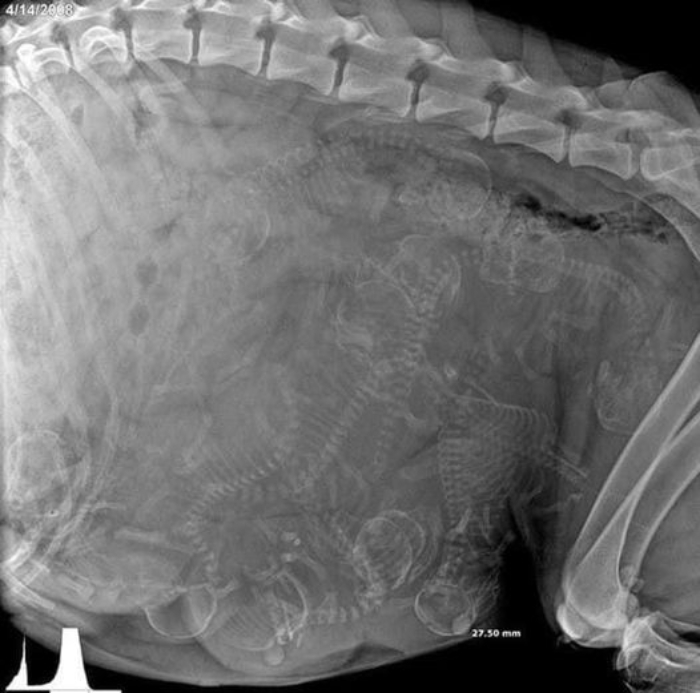

Radiografía de una perra embarazada